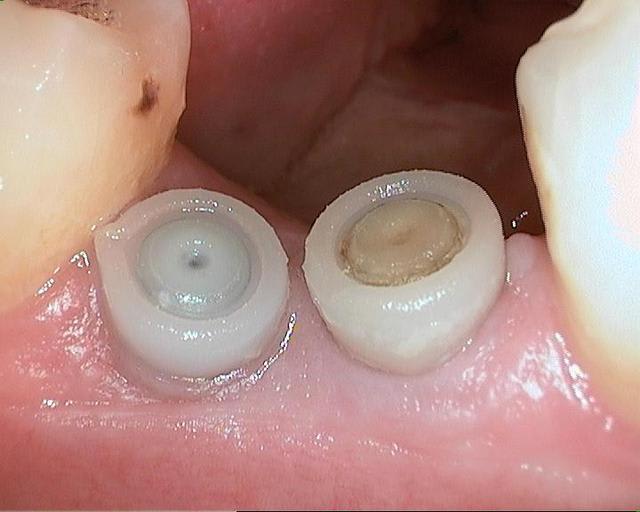

des photos d'un cas d'aujourd'hui avec le shuttle retiré ( 8 premières photos)

les 4 dernières c'est avec le foret , la dernière photo c'est un cas d'extraction implantation d'aujourd'hui aussi on voit la nouvelle alvéole après le forage ( désolé pour la qualité de photo...)